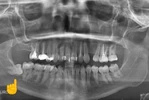

Diş Çürükleri

Diş Eksikliği

Diş ve Diş eti hastalıkları

Periimplantitis